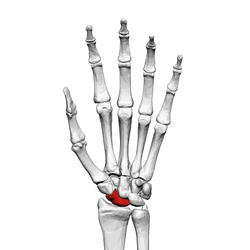

![]() Left hand anterior view (palmar view). Scaphoid bone shown in red. | |

The scaphoid bone /ˈskæfɔɪd/ (from the Greek word scaphoides, boat-shaped) is one of the carpal bones of the wrist. It is situated between the hand and forearm on the thumb side of the wrist (also called the lateral or radial side). It forms the radial border of the carpal tunnel. The scaphoid bone is the largest bone of the proximal row of wrist bones, its long axis being from above downward, lateralward, and forward. It is approximately the size and shape of a medium cashew.

The scaphoid is situated between the proximal and distal rows of carpal bones. It is located on the radial side of the wrist, and articulates with the radius, lunate, trapezoid, trapezium and capitate.[1] :176 Over 80% of the bone is covered in articular cartilage.[2]